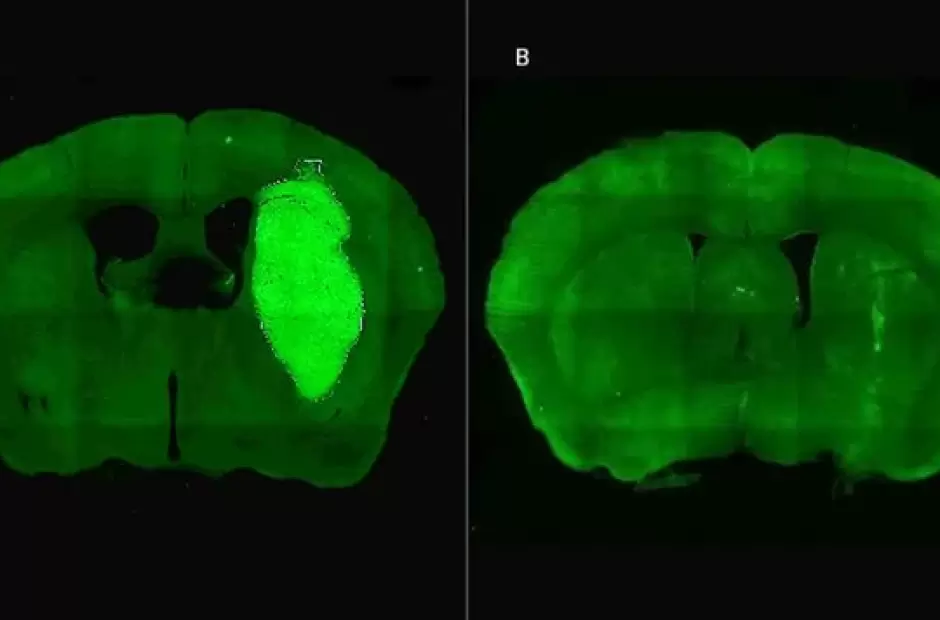

Un equipo de investigadores del Consejo Nacional de Investigaciones Científicas y Técnicas (CONICET) logró, mediante una innovadora estrategia terapéutica, frenar el avance del glioblastoma, el tumor cerebral primario maligno más frecuente en adultos y uno de los más resistentes a los tratamientos convencionales.

El estudio, publicado en la revista Life Sciences, demostró que el bloqueo de una proteína llamada Foxp3 —presente en las células del glioblastoma— aumenta significativamente la sensibilidad del tumor a la quimioterapia y la radioterapia. En la actualidad, la mediana de supervivencia para los pacientes diagnosticados con este cáncer es de apenas 9 meses, con una tasa de sobrevida a cinco años del 7%.

Los ensayos, realizados en modelos celulares murinos y humanos —incluidos cultivos derivados de biopsias de pacientes desarrollados en el Instituto FLENI—, mostraron que P60 no solo mejoró la respuesta del glioblastoma a radioterapia y diversas drogas quimioterapéuticas, sino que también redujo directamente la viabilidad y migración de las células tumorales, e inhibió el crecimiento de vasos sanguíneos que lo nutren.